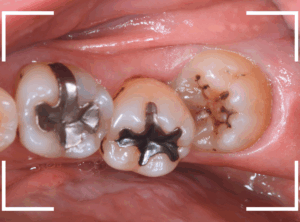

少し歯と歯の境を削ったところです。

食物残差と虫歯でひどい状況になっているのがわかります。

治療も大変ですが、経過観察していても状況は良くなりませんので、あと一息、頑張りましょう!